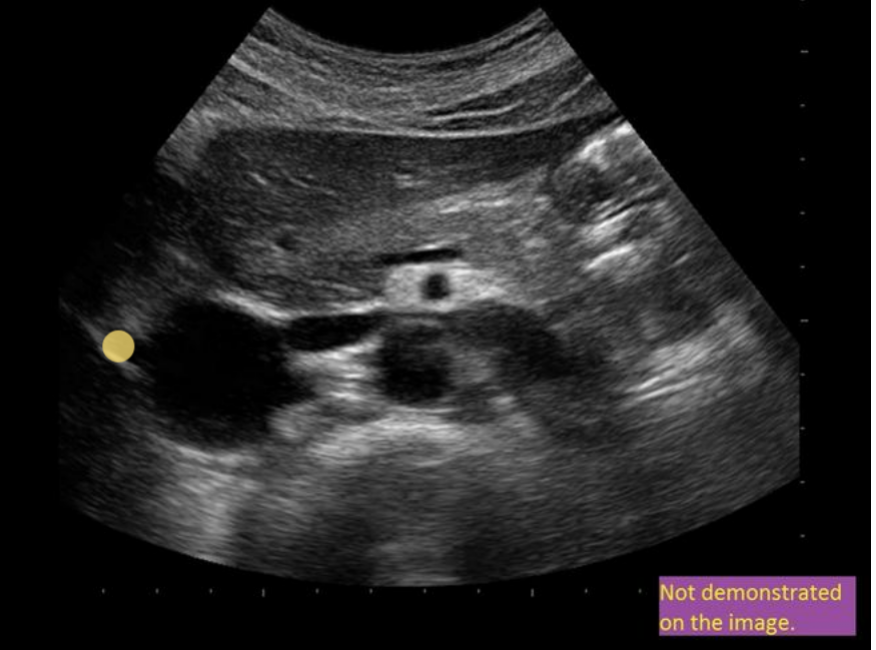

this image is

.

a) incorrect label + diameter

b) correct label; incorrect diameter

c) correct label; correct diameter

d) incorrect label; correct diameter

a. incorrect label + diameter